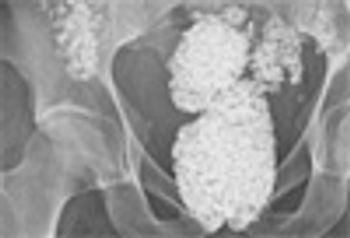

Gout, once considered a disease of kings, is now a common and equal opportunity disease that affects as many as 3 million people in the US. Gouty arthritis has now become a serious problem in organ transplant recipients; in diuretic users; and in patients with CKD, hypertension, metabolic syndrome, heart failure, plus more.